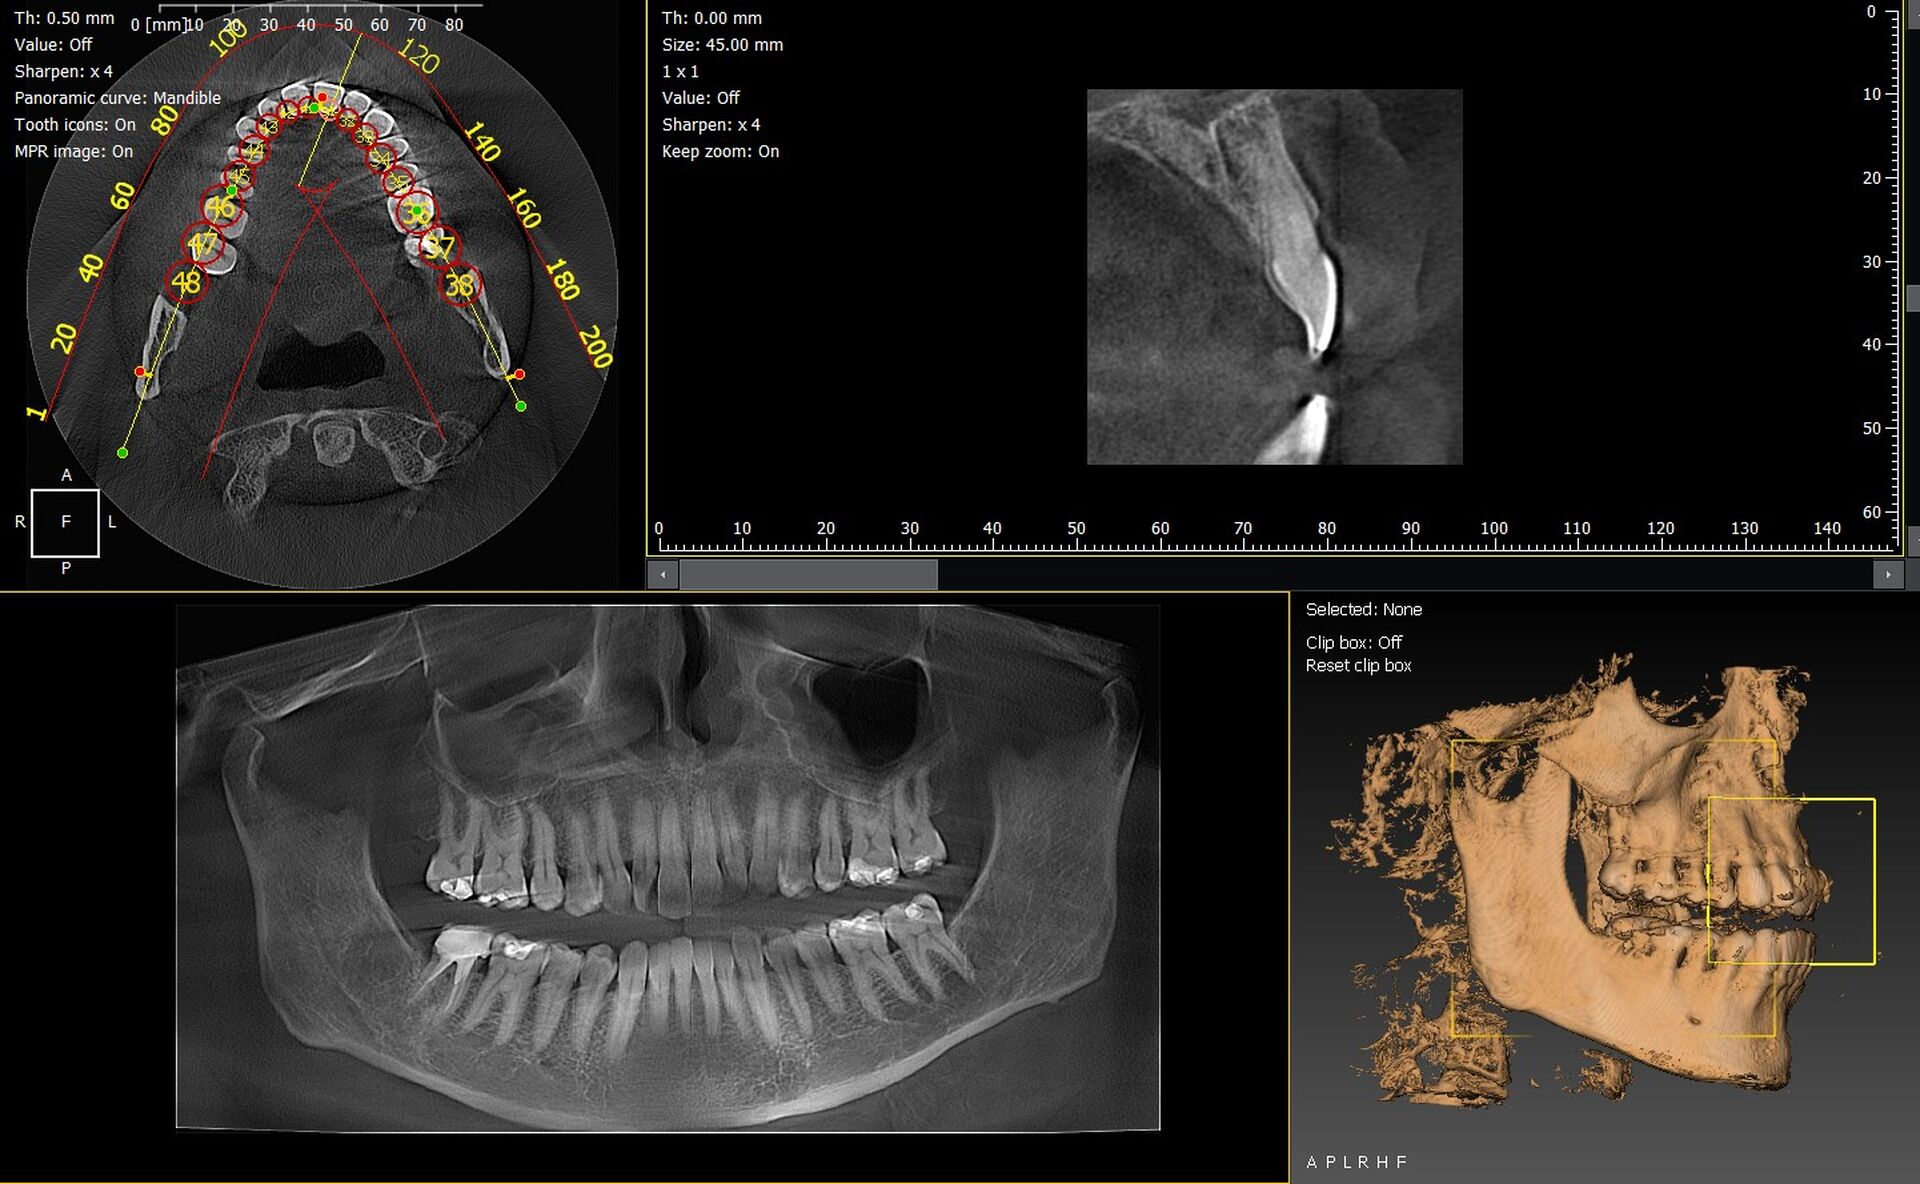

Les cabinets dentaires de Cannes et du département des Alpes-Maritimes (06) renforcent leur plateau technique grâce à des solutions d’imagerie 3D fiables et performantes. Les panoramiques CBCT 3D VistaVox de Dürr Dental et l’Owandy I-Max 3D figurent parmi les appareils les plus avancés, offrant une qualité d’image optimale et un diagnostic précis.

VistaVox 3D : précision et optimisation du volume

Le VistaVox se distingue par :

• un champ d’exploration parfaitement adapté à l’arcade,

• une résolution élevée idéale pour implantologie et endodontie,

• une réduction de dose maîtrisée,

• un positionnement rapide du patient.

Owandy I-Max : compact, intuitif et polyvalent

L’Owandy I-Max 3D est apprécié pour :

• son design mural compact,

• ses protocoles 2D/3D rapides,

• son excellente qualité d’image,

• sa simplicité d’utilisation.